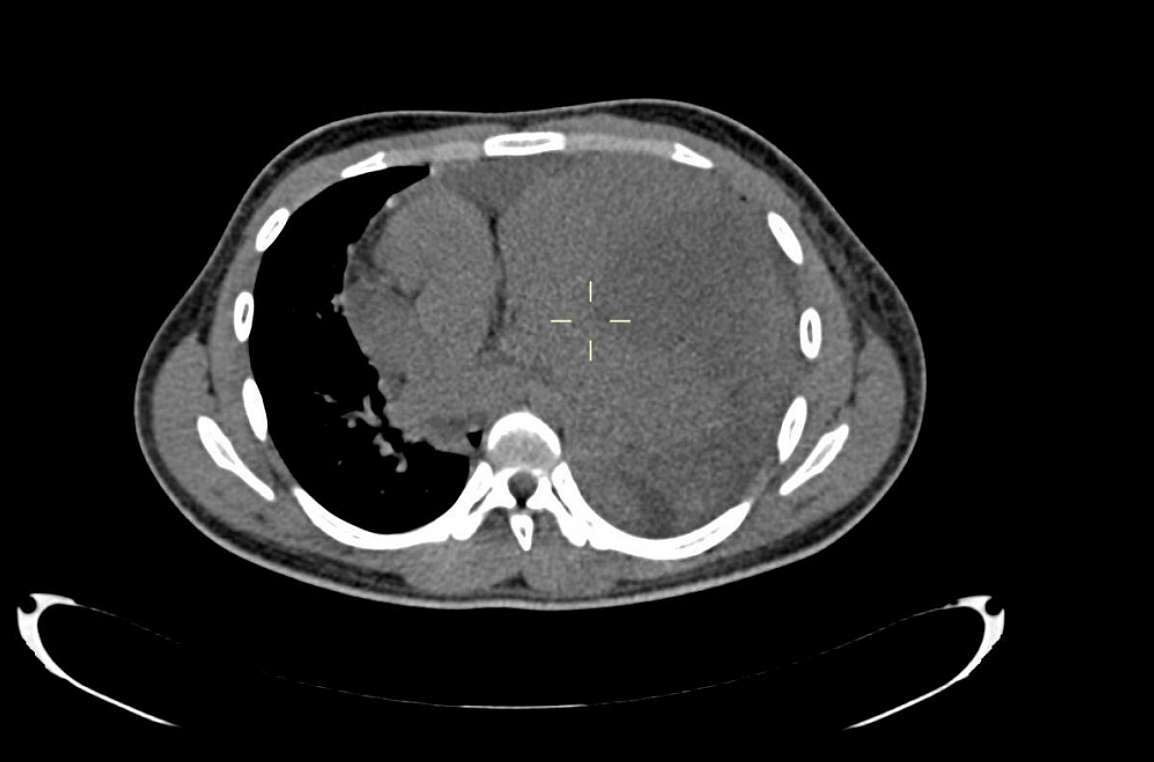

Thoracic and abdominal computed tomography with and without IV contrast demonstrated a 16 x 13 x 10 cm heterogeneous enhancing anterior mediastinal mass lesion without fat or calcifications but areas of necrosis. The mediastinal structures and heart were displaced towards the right side. There was a compression atelectasis of the left lung, a minimal pleural effusion on the left side and a moderate pericardial effusion.

CT demonstrates a smooth, lobulated soft tissue attenuating bulky mass, with areas of necrosis. Other features include parenchymal invasion, pleural effusion, pericardial effusion, chest wall invasion, tracheal, oesophageal and vascular compression. However, it is difficult to differentiate primary mediastinal large B-cell lymphoma from Hodgkin lymphoma and lyphoblastic lymphoma on the basis of imaging findings alone [1]. Histopathology and immunohistochemistry are necessary to distinguish these entities [2].